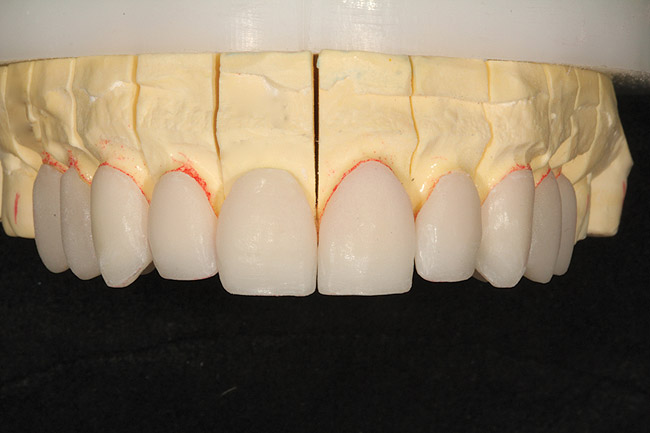

Figure 25  Through the lost-wax process, the IPS e.max restorations were pressed and then fitted to the master dies.

Figure 25

Figure 26  View of the lingual aspect of the fitted IPS e.max restorations on the master dies.

Figure 26

After receiving the provisional records, impressions, and eyebrow-to-chin photographs of the patient smiling with the provisionals in place (fabricated in plastic), a Sil-Tech® (Ivoclar Vivadent) matrix was formed over the cast of the provisionals and placed in a pressure chamber. This matrix then was used as a mold to inject wax onto the treated and lubricated master dies (Figure 24). Through the lost-wax process, the final restorations were produced using IPS e.max Press lithium-disilicate glass-ceramic. Impulse V1 was pressed at a temperature of 915° C (Figure 25 and Figure 26.).